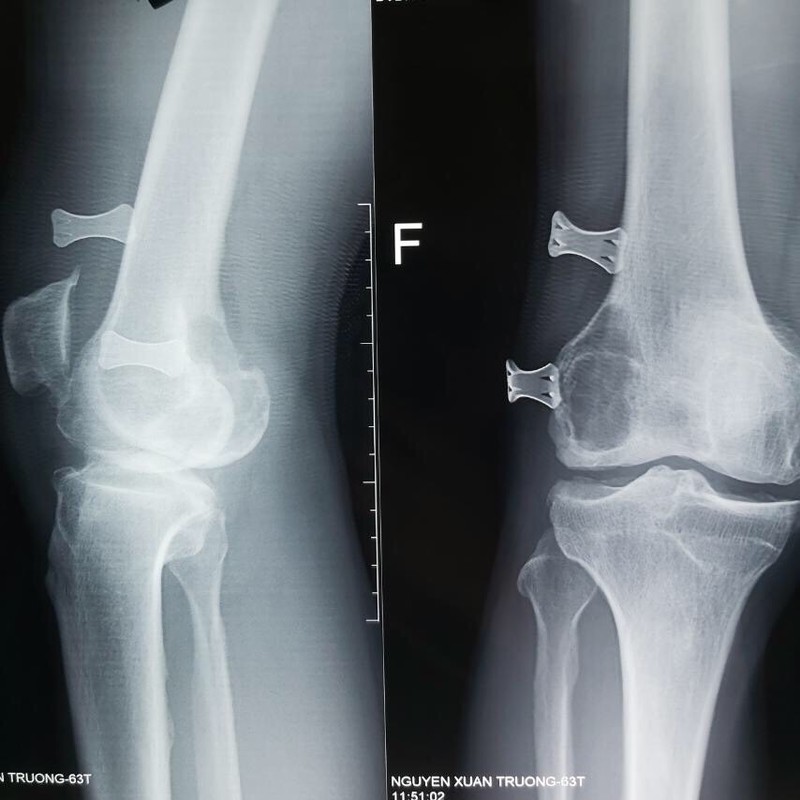

Bệnh nhân là ông N.X.T., 63 tuổi, sống ở phường Kỳ Bá, TP. Thái Bình. Trước đó, ông T. có tiền sử đau khớp gối đã 5 năm. Ông T. đã đi nhiều bệnh viện khác và chỉ điều trị nội khoa. Trước khi đến Bệnh viện Hữu nghị Việt Đức1 tuần, ông T. trượt chân ngã, đau đớn, không thể vận động nhiều, khớp gối chỉ gấp được 20°, trong khi bình thường khớp gối có thể gấp được 100° - 120°. Trên phim X-quang cho thấy bệnh nhân vừa bị thoái hóa khớp gối vừa có một khối u ở lồi cầu ngoài xương đùi.

Phim chụp X-quang khớp gối của bệnh nhân (Ảnh: BVCC)

Theo BS. Khánh, người bệnh bị u xương từ lâu nhưng bị bỏ sót. Trước đó, ông T. chỉ đi khám vì một thoái hóa khớp gối và chỉ điều trị nội khoa. Khi để lâu, u xương đã phá hủy, chỉ cần một chấn thương nhẹ cũng gây ra gãy phần xương đó, mà lại gãy xương trên nền thoái hóa khớp gối, thay khớp gối sẽ trở nên khó khăn hơn rất nhiều, vì đồng thời phải xử lý mấy thương tổn cùng một lúc, vừa lấy u, vừa xem u phá hủy xương đến đâu, vấn đề ghép xương, vấn đề dự trù trang thiết bị dụng cụ khớp để lắp vào khớp gối sẽ khó khăn hơn rất nhiều so với những người bệnh chủ động.